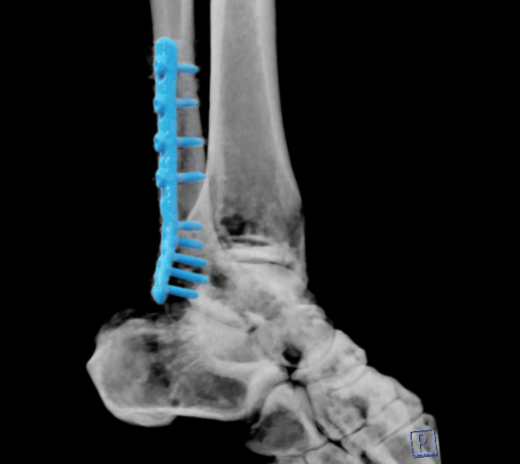

• 泌尿科与骨科:肾石分类、关节尿酸结晶分析。

踝关节